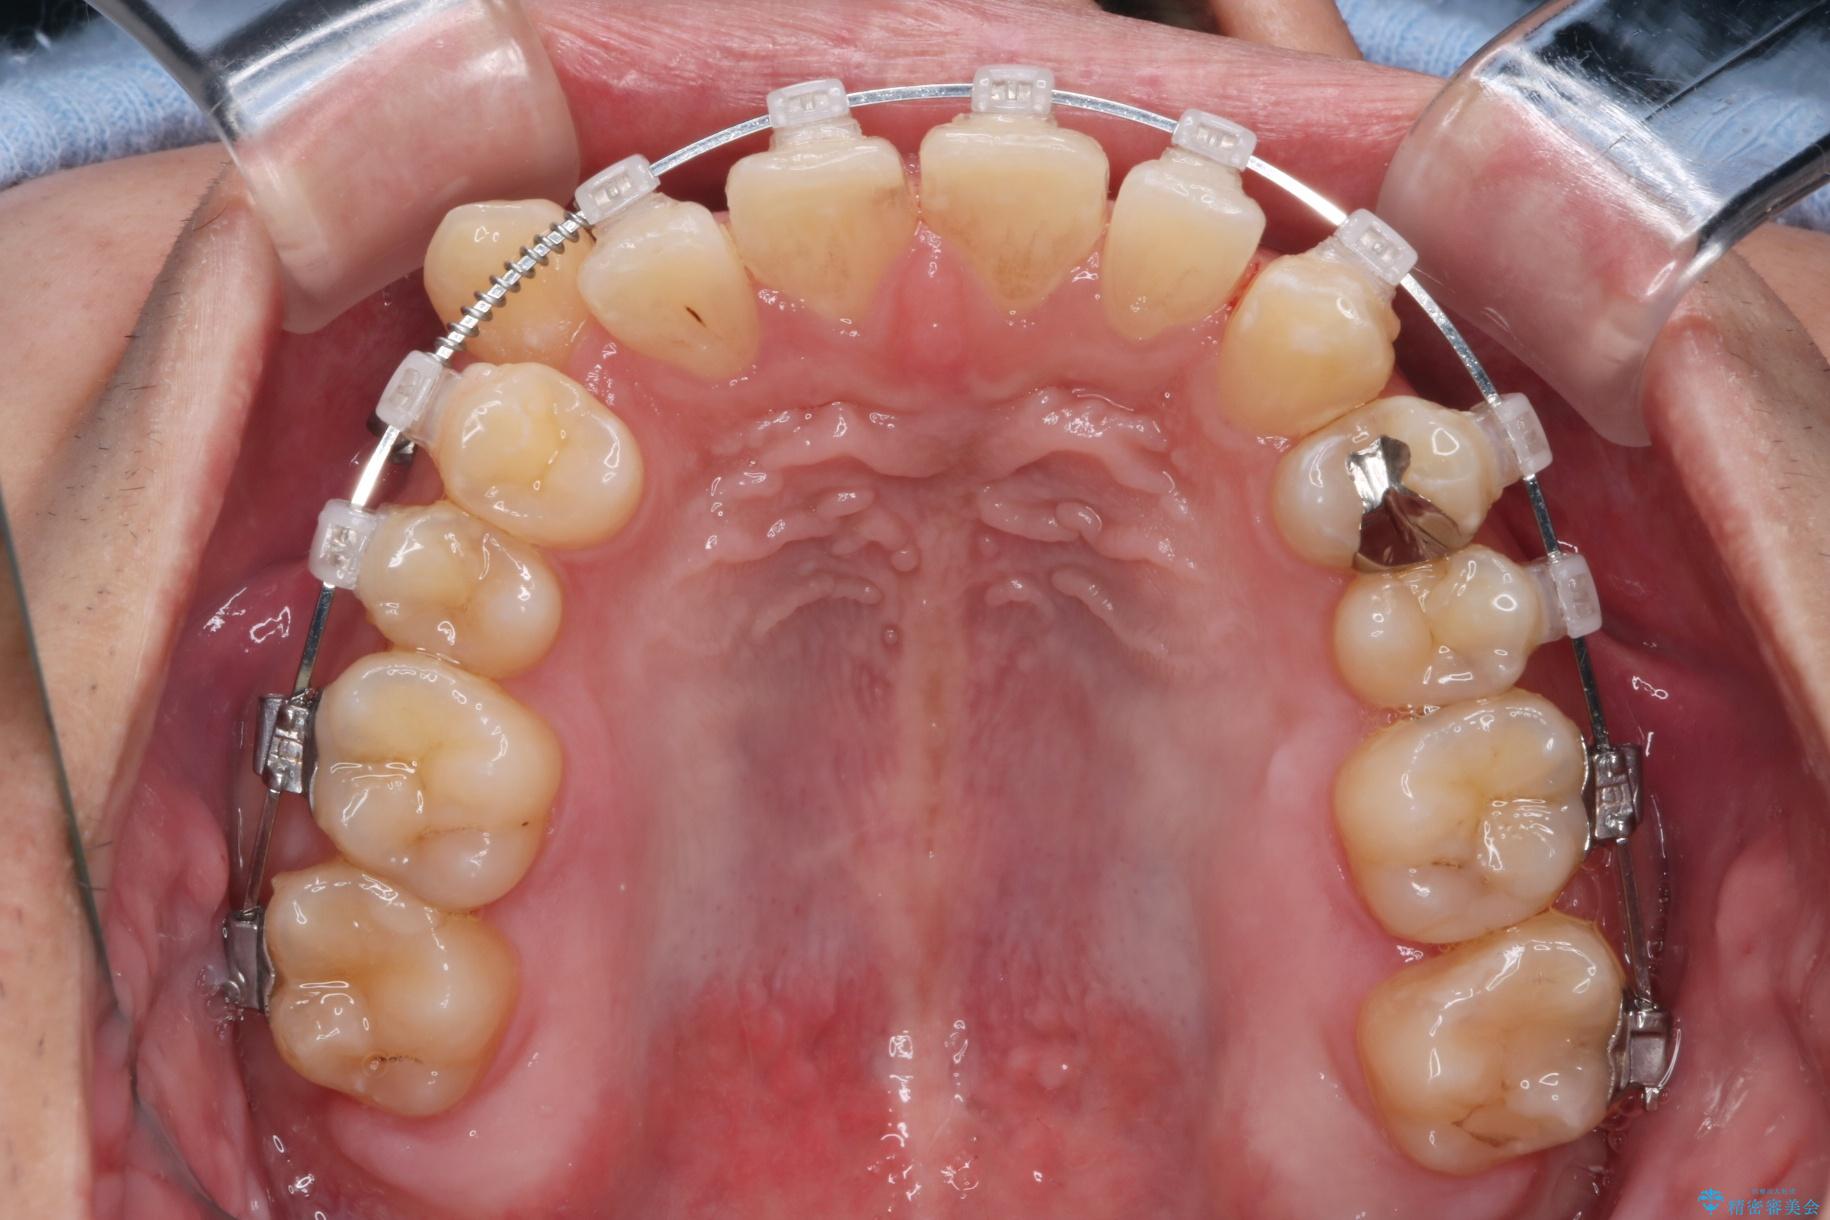

精密検査の結果、抜歯の必要はないと判断しました。臼歯を遠心移動させ、歯列をワイヤーで整えることでスペースを確保し、IPR(歯と歯の間を削る処置)を加えて歯並びを綺麗にする治療計画を立てました。

歯の移動にオープンコイルとMI(歯肉に埋入するネジ)を用いました。